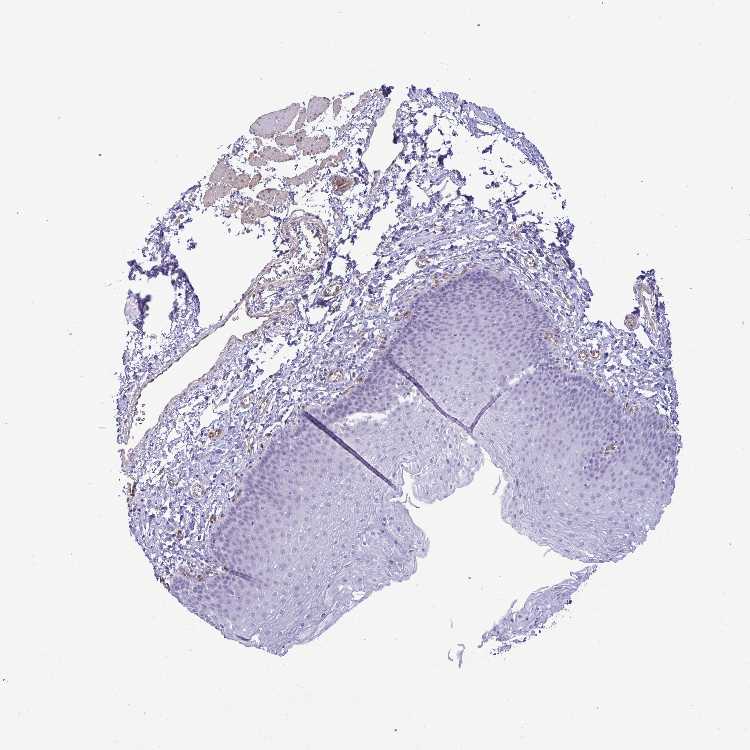

ESOPHAGUS - Antibody stainingi

Antibody staining in the annotated cell types in the current human tissue is reported as not detected, low, medium, or high, based on conventional immunohistochemistry profiling in selected tissues. This score is based on the combination of the staining intensity and fraction of stained cells.

Each image is clickable and will lead to virtual microscopy that enables deeper exploration of all samples and also displays staining intensity scores, fraction scores and subcellular localization as well as patient and tissue information for each sample.

Antibody HPA058340

Squamous epithelial cells Not detected